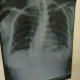

Alo Dokter, izin bertanya, seorang wanita berusia 27 tahun bertanya apakah memungkinkan beliau hamil dalam kondisi mengalami skoliosis. Beliau melakukan cek mandiri, namun belum ke dokter saraf ataupun dokter ortopedi untuk konsul lebih lanjut karena takut dioperasi. Saat ini pasien ingin sekali hamil, namun khawatir nanti akan bermasalah atau tidak pada kehamilannya ataupun persalinannya. Mohon infonya Dokter, terimakasih sebelumnya.